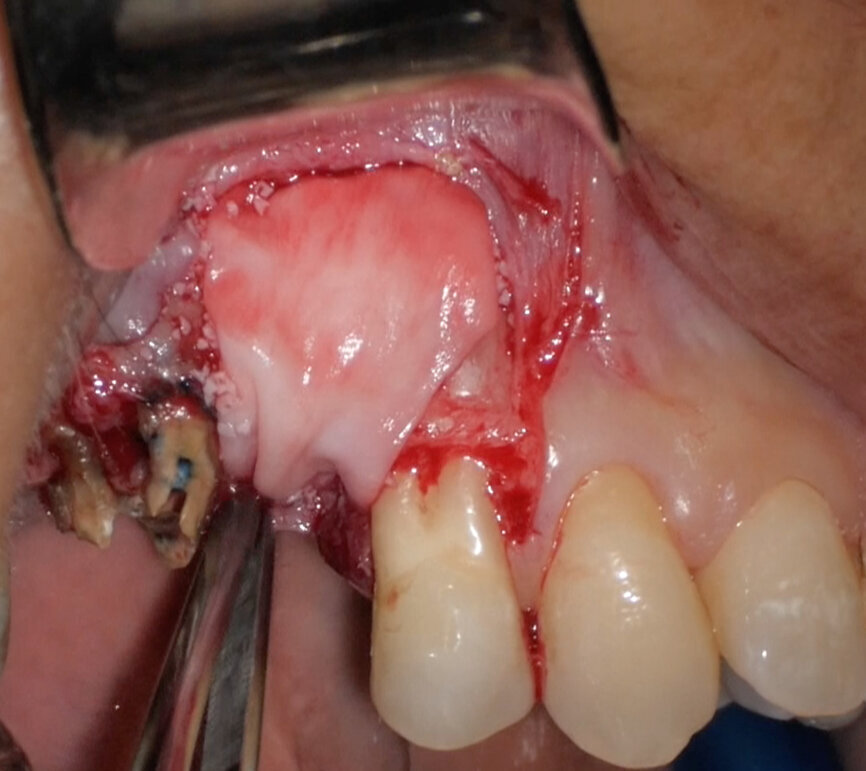

Preoperative CBCT evaluation is useful in cases requiring a surgical approach, not only in order to confirm the presence of a lesion but also to plan the procedure and, in particular, identify the type of surgical incision to be used, based on its size and location (Figs. 23–25). This specific case is characteristic of this situation. The intraoral radiograph did not make it possible to ascertain the extent of the lesion, which involved not only the apical region of the premolar but also a distal edentulous segment. This region would need to be treated with regenerative therapy in order to guarantee correct healing of the area, with subsequent insertion of a membrane, the flap must be protected using a totally different approach to that required for endodontic surgery. The intraoperative images illustrate the various stages of the procedure (Figs. 26–28). The CBCT scan performed 12 months later confirmed complete healing of the apical lesion and perfect graft integration (Figs. 29–31).